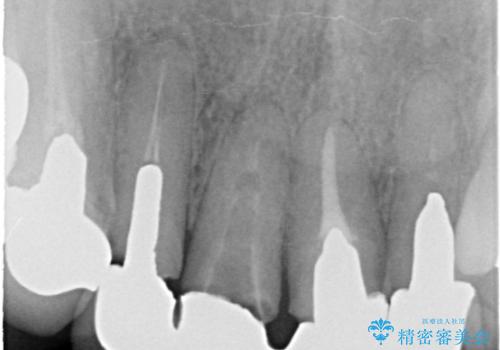

レントゲンを撮影すると、適合不良のかぶせ物が装着されており、根の治療も不十分であることが確認されました。

適合不良のかぶせ物をすべて除去して、根の中の治療から再治療を行うこととなりました。